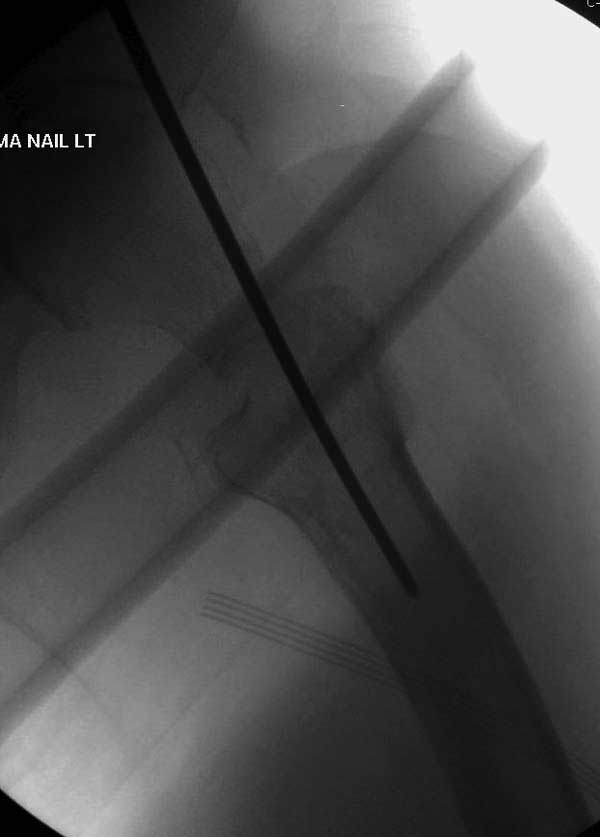

Первые снимки показывают технические погрешности установки DHS. Не была достигнута репозиция, конечность в флексии и шейка в ротации. Сегодня все меньше обращают внимание на параметры для оценки репозиции (S контуры Lowell в обеих проекциях и Garden Alignment Index, в норме 155 и 180 градусов), хотя такие простые тесты помогли бы дорепонировать смещение. Винт находится сзади в головке, что при нагрузке поменяет вектор и вместо компрессии в линии перелома срежет головку-Cut Out!

Повторно поступает после двух с половиной лет, где обнаруживается перелом на второй стороне. Немного сложно, но для фиксации выбрали Antegrade InterTan Smith Nephew Nail и с момента фиксации более 3х мес.